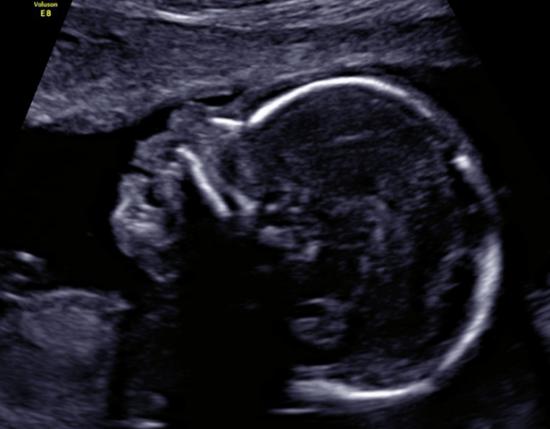

- badanie II trymestru (USG) wykonywane między 18-23 t.c.

Badanie to polega na ocenie anatomii płodu. Ponadto wykonana zostanie biometria i oszacowana masa płodu, sprawdzona funkcja łożyska oraz ilość płynu owodniowego.